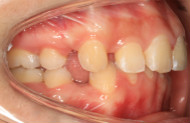

“以前牙不齐,两颗上门牙有点突,被人说是‘老鼠牙’,还有深覆颌(刚开始我不懂,后来做了小百科哈,如果你们跟我一样,牙齿咬合状态时,上门牙盖住了下门牙,超过了1/3就被称为深覆合),导致了我每次拍照的时候从来都不笑,一定要笑,也是笑不露齿的那种。

开门见山,20岁,坐标广东,“以前牙不齐,两颗上门牙有点突,被人说是‘老鼠牙’,还有深覆颌(所谓的深覆合就是牙齿咬合状态时,上门牙盖住了下门牙,一般1/3是比较正常的,超过了1/3就被称为深覆合),导致了我每次拍照的时候从来都不笑,一定要笑,也是笑不露齿的那种。”真的很像假笑女孩~[○・`Д´・ ○].牙齿不齐,对口腔清洁也是非常遭罪,这个本人是深有体会啊

今天来说说戴牙套感受吧,3-5天的时候还是有一点酸软,不能吃骨头、鸡爪这些硬的东西,习惯了之后觉得没什么了。现在就是吃什么都无所谓。身边的人也完全没有‘另眼相看’,可能是因为周围人也都是学医的,好几个朋友也在矫牙,大家都习以为常。矫了牙后,露出牙套也丝毫不在意,自己感觉比之前爱张嘴笑了,笑起来也自信大方,没有以前沉默不笑的样子了。期待牙齿渐渐排齐的样子(*^▽^*)